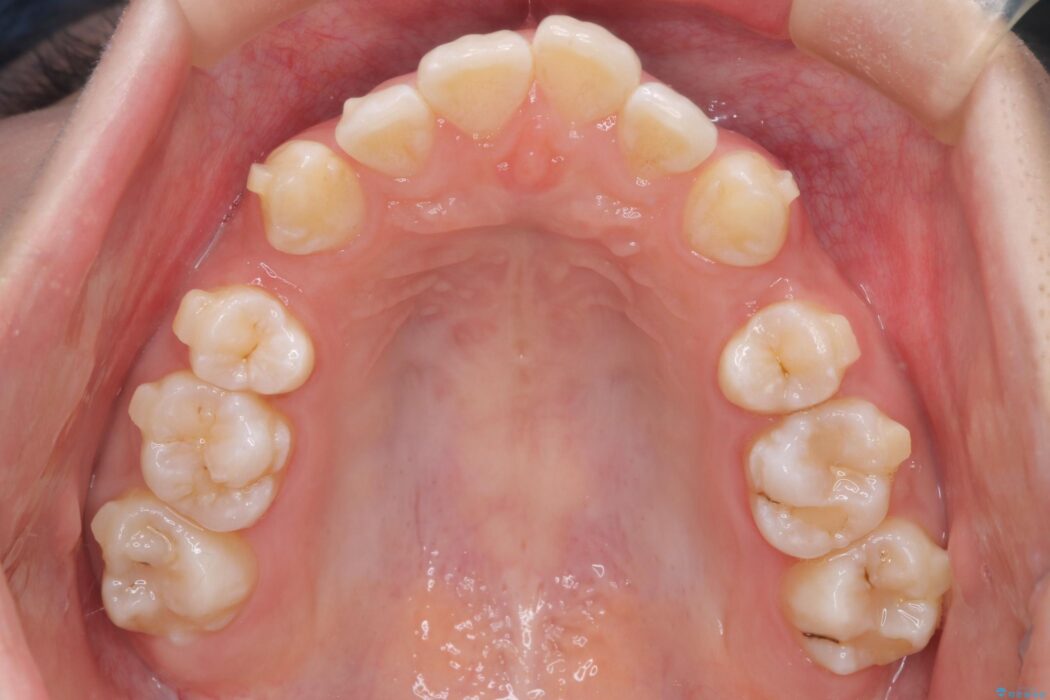

前歯から奥歯にかけて重度のがたつきを主訴にご来院された患者様です。

スペースが大きく不足し、口元を引っ込める必要があったため、上下左右4本抜歯による矯正治療を計画。目立たないインビザライン装置で、審美的なゴールを目指します。